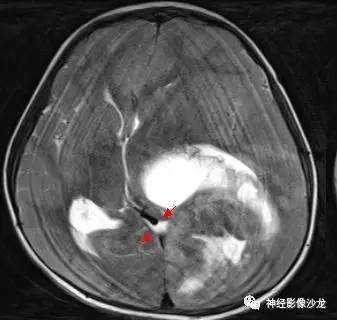

箭头标注的地方是左侧脑室后角吧?

这里应该是侧脑室后角

T1像有点状高信号

就对应钙化

这些都是钙化吧

CT是钙化

T1WI点状高信号

出血点哪位老师标注下[抱拳]

侧脑室三角区受压